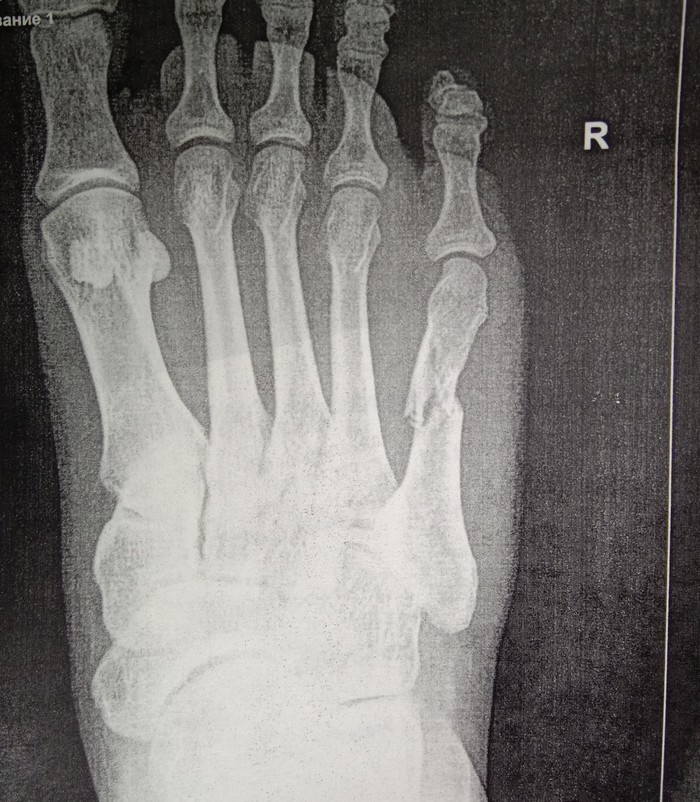

Приехали, взяли талон и направились к травматологу. В кабинете врач осмотрев ногу, направил меня на рентген. И вот увидев снимок, мои опасения подтвердились.

Принесла снимки врачу, он говорит, надо вправлять ,перелом со смещением. Отправляет меня в процедурную (или как там правильно называется), я попросила врача, чтоб дедушка пошел со мной, мол с родней не страшно будет. Вот сидим с дедом смеемся над всей ситуацией, фоткаем друг друга,мол на память. И тут заходит врач, садится ко мне на кушетку и начинает протирать ногу спиртом. И тут начинается кино)) Мне становится дурно и я прошу просто полежать. Все, темнота. Очнулась когда меня уже посадили, вся мокрая и бледная. Вокруг меня бегают несколько врачей, измеряют давление ,смотрят зрачки, а я вроде и пришла в себя, но ничего понять не могу.

Понедельник, мы с мужем в приемном покое встречаем врача. Объясняем ему все , он отправляет нас на рентген. Но увы и ах, кость встала ровнее, но "домик"остался. Идем в процедурную, там мне вправляют кость, делают гипс и опять на рентген. Нога встала чуть ровнее, но может "соскочить " в любой момент. В общем надо вставлять спицу.

Вот как установили мне саму спицу. 3 мая надо вытаскивать. Швы по идее надо снять уже завтра, но в поликлинике мне сказали, что они не знают, сможет ли принять меня врач, у него все по записи.